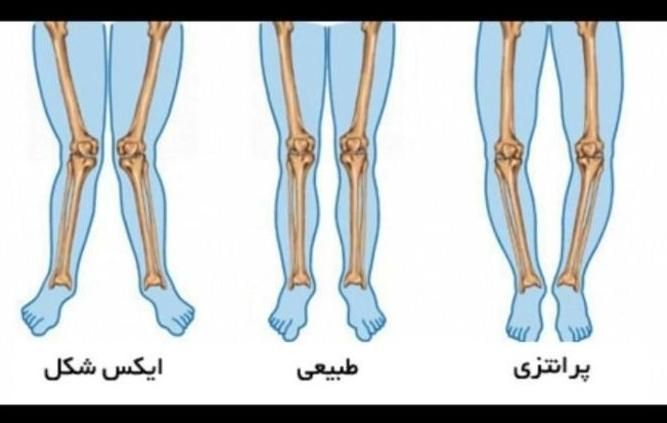

مرکز تخصصی اصلاح ناهنجاریهای اسکلتی با بیش از 15 سال تجربه درخشان زیر نظر متخصص دارای مدرک FTC از مراکز انگلیس و امارات ✅ خدمات ما: • درمان کف پای صاف و قوسدار • اصلاح پای ضربدری و پرانتزی • درمان گودی و دیسک کمر . گودی کمر و قوز • رفع درد زانو و مفاصل • درمان آرتروز و شانه یخ زده • بهبود واریس و سلولیت ویژگیهای منحصر به فرد ما: • ارائه روش اختصاصی براساس شرایط هر فرد • استفاده از متدهای نوین و علمی • پشتیبانی مستمر در طول دوره درمان • ارائه گزارش پیشرفت ماهانه شرایط پرداخت منعطف: • امکان پرداخت اقساطی • تخفیفهای ویژه سازمانی ☆ قیمت هر جلسه یکو نیم میلیون (۱/۵۰۰/۰۰۰ تومان) دوره های (۸جلسه)، (۱۶ جلسه)، (۲۴ جلسه)، (۳۰جلسه)، (۳۶ جلسه) و (۴۲ جلسه) آدرس: سبزه میدان، انتهای پیغمبریه، ساختمان هانا، مجموعه هانا ☆ برای مشاوره حضوری و تعیین وقت ؛ (نام و نام خانوادگی و شماره تماس) خود را در چت دیوار ارسال کنید و یا به شماره آگهی اس ام اس کنید. ☆ عزیزان هر سوالی داشتین از ساعت 11 صبح الی 10 شب تماس بگیرین در خدمتتون هستم. دکتر شاهمحمدی سلامتی شما، تخصص ماست